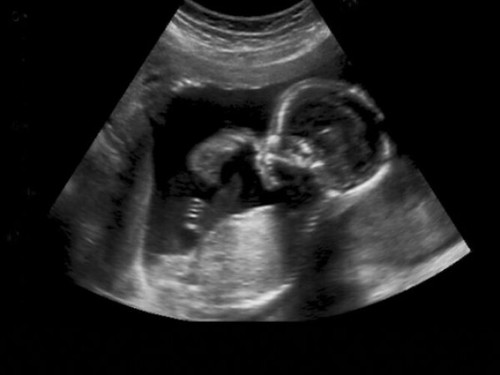

How did you feel when you saw your baby on the first scan?

Amazed, in awe & wonder, and excited

so excited.. happy..blessed

love